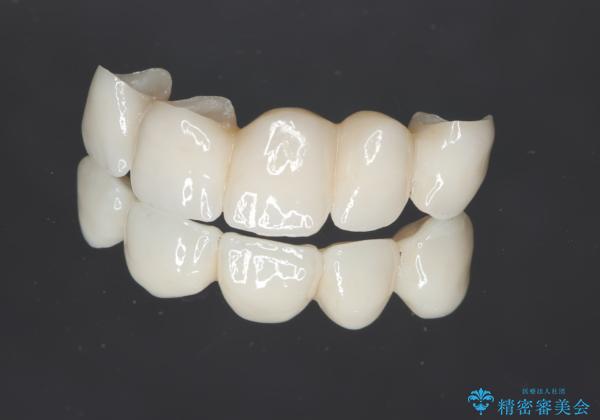

- 66万円(ジルコニアクラウン×5・仮歯×5)費用は治療当時の料金となります